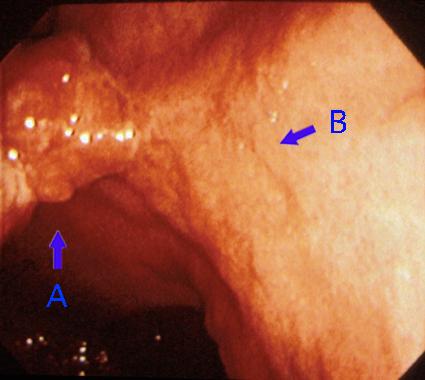

以隆起为主体的5型胃印戒细胞癌内窥镜照片   以胃体部为中心的内窥镜照片。可见在胃体中部小弯存在一个明显的隆起(箭头A),其表面有分叶,被白苔覆盖,有糜烂形成。另外,和这个隆起(A)相连,在后壁还可见有一个浅凹陷(B)。这个浅表面凹陷的形状和边缘不整,呈癌的特症。

疾病(病理主体)的分类恶性上皮性肿瘤/印戒细胞癌

部位(按器官分)胃(部位)/体部

肿瘤的肉眼分类5型(难以分类)/

肿瘤最大直径40以上

肿瘤的深度mp